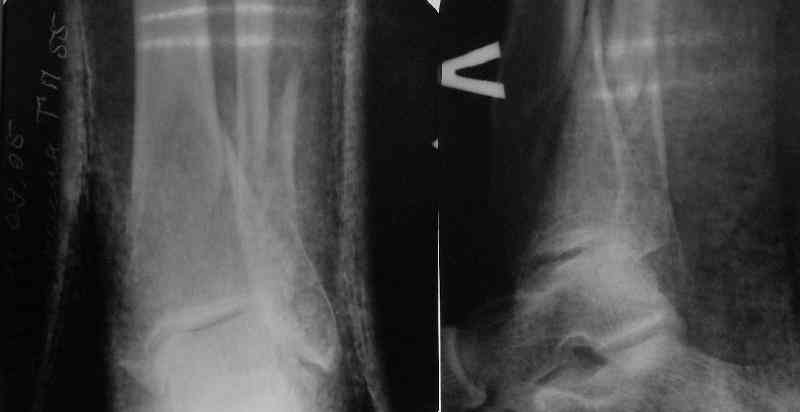

A typical case is attached, also an image with intra-op reduction obtained by a small wire distractor, in the moment of insertion a Poller wire in AP direction. Fixation by a SIGN nail. Despite the fibula was not fixed healing was obtained with the unchanged alignment.

Отправитель: T. Derek V. Cooke 21 Май 2006, 23:18

Alex:

Отправитель: Alexander Chelnokov 21 Май 2006, 23:21

TDVC> Very interesting application, but is the final position in a

TDVC> little distal varus with some fibula distraction?

At least both the ankle mortise and tibial alignment look acceptable, don't they?

TDVC> Would that have been eliminated by fibula plating?

I am just trying to illustrate that prevention of 1)tibial valgus and 2)loss of reduction can be provided without fibular plating. Small changes of conventional nailing techniques allow to maintain reduction of the tibia reliably without adjunctive fibular stabilization.

In delayed cases acute length restoration performed only in the tibia may leave the fibula shortened thus change the mortise. So it is reasonable to restore length of both bones simultaneously by distractor and fix the fibula not with open reduction and plating but just by a single perQ screw. Example attached.